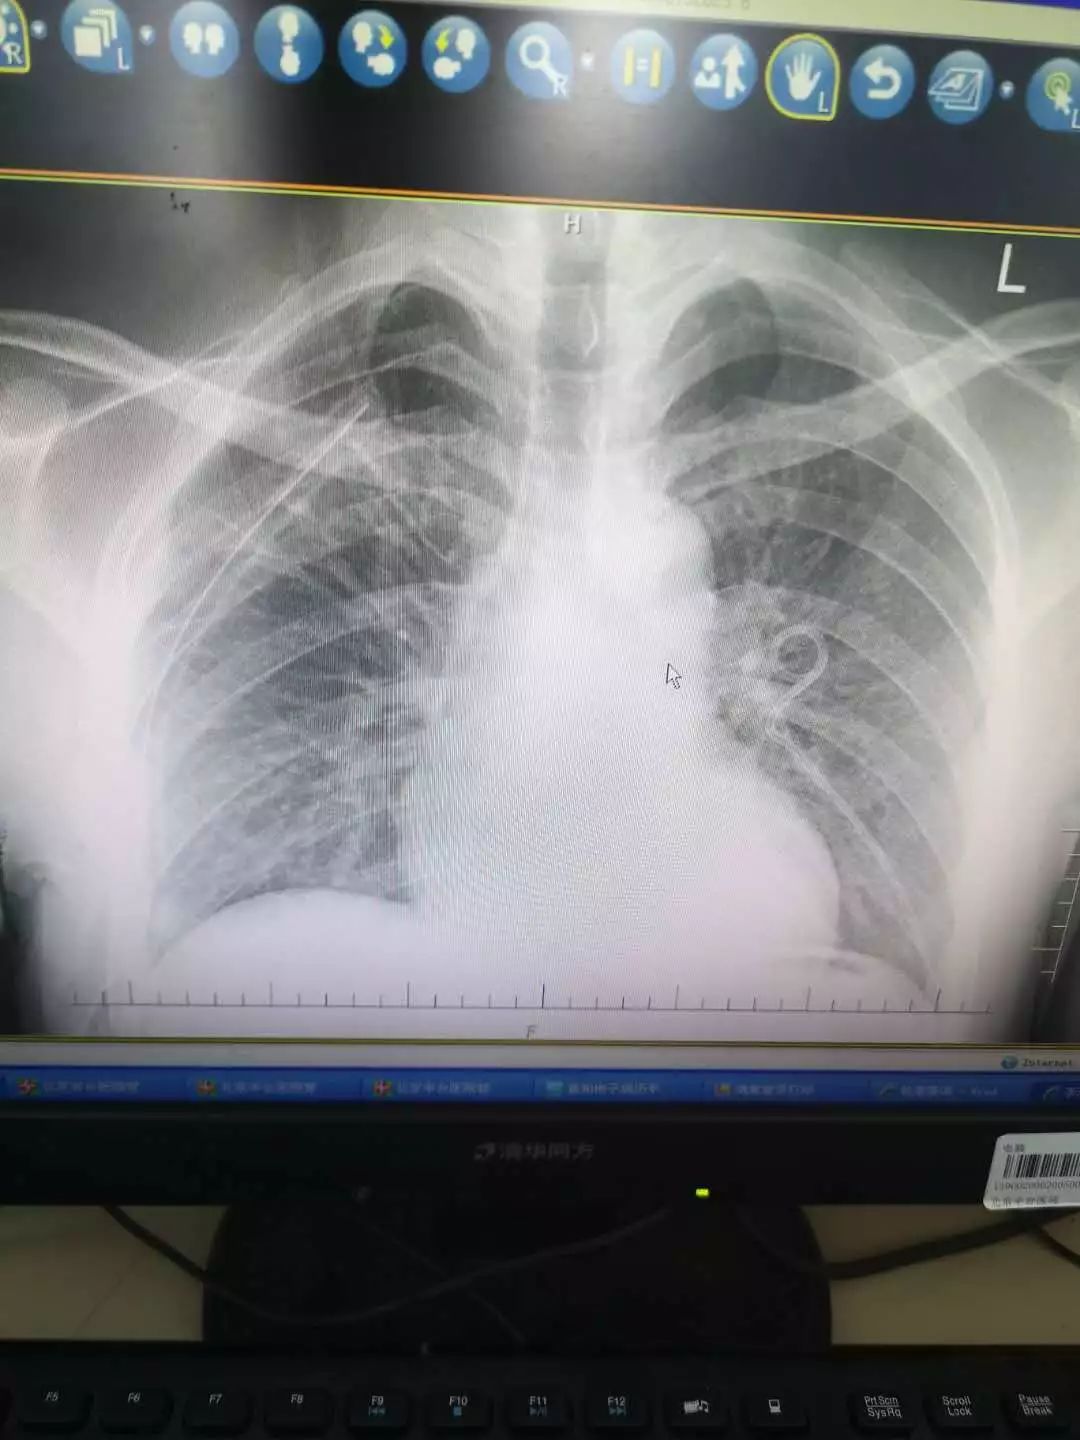

男,61岁,咳嗽,胸部平片示右肺门增大,请老师们帮忙看下

随后进行的胸部 ct 也证实了这一点,胸部 ct 显示:右肺下叶及右中叶实